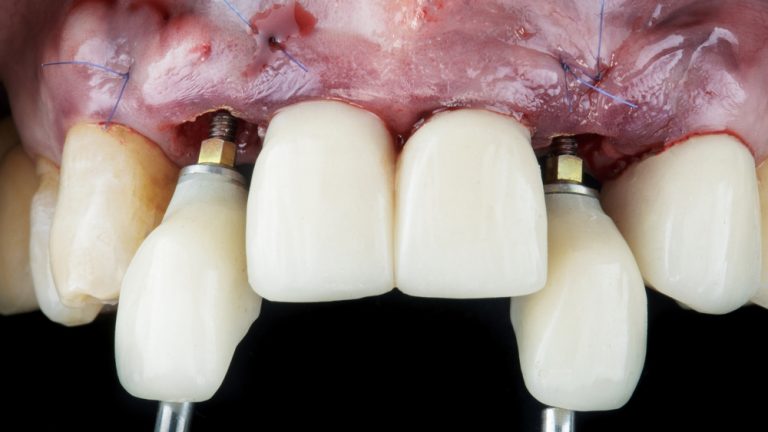

Consiste en insertar un tornillo de titanio en el hueso de la mandíbula o el maxilar, que actúa como raíz del diente y sirve de soporte para una corona, puente o prótesis dental.

Se insertan y se colocan las prótesis dentales en el mismo día o en pocos días, permitiendo al paciente usar sus nuevos dientes de inmediato.

Colocación de implantes de carga inmediata

Consiste en exponer los implantes después de su integración ósea y colocar los pilares que servirán de soporte para las prótesis definitivas.

Cirugía de Conexión de implantes